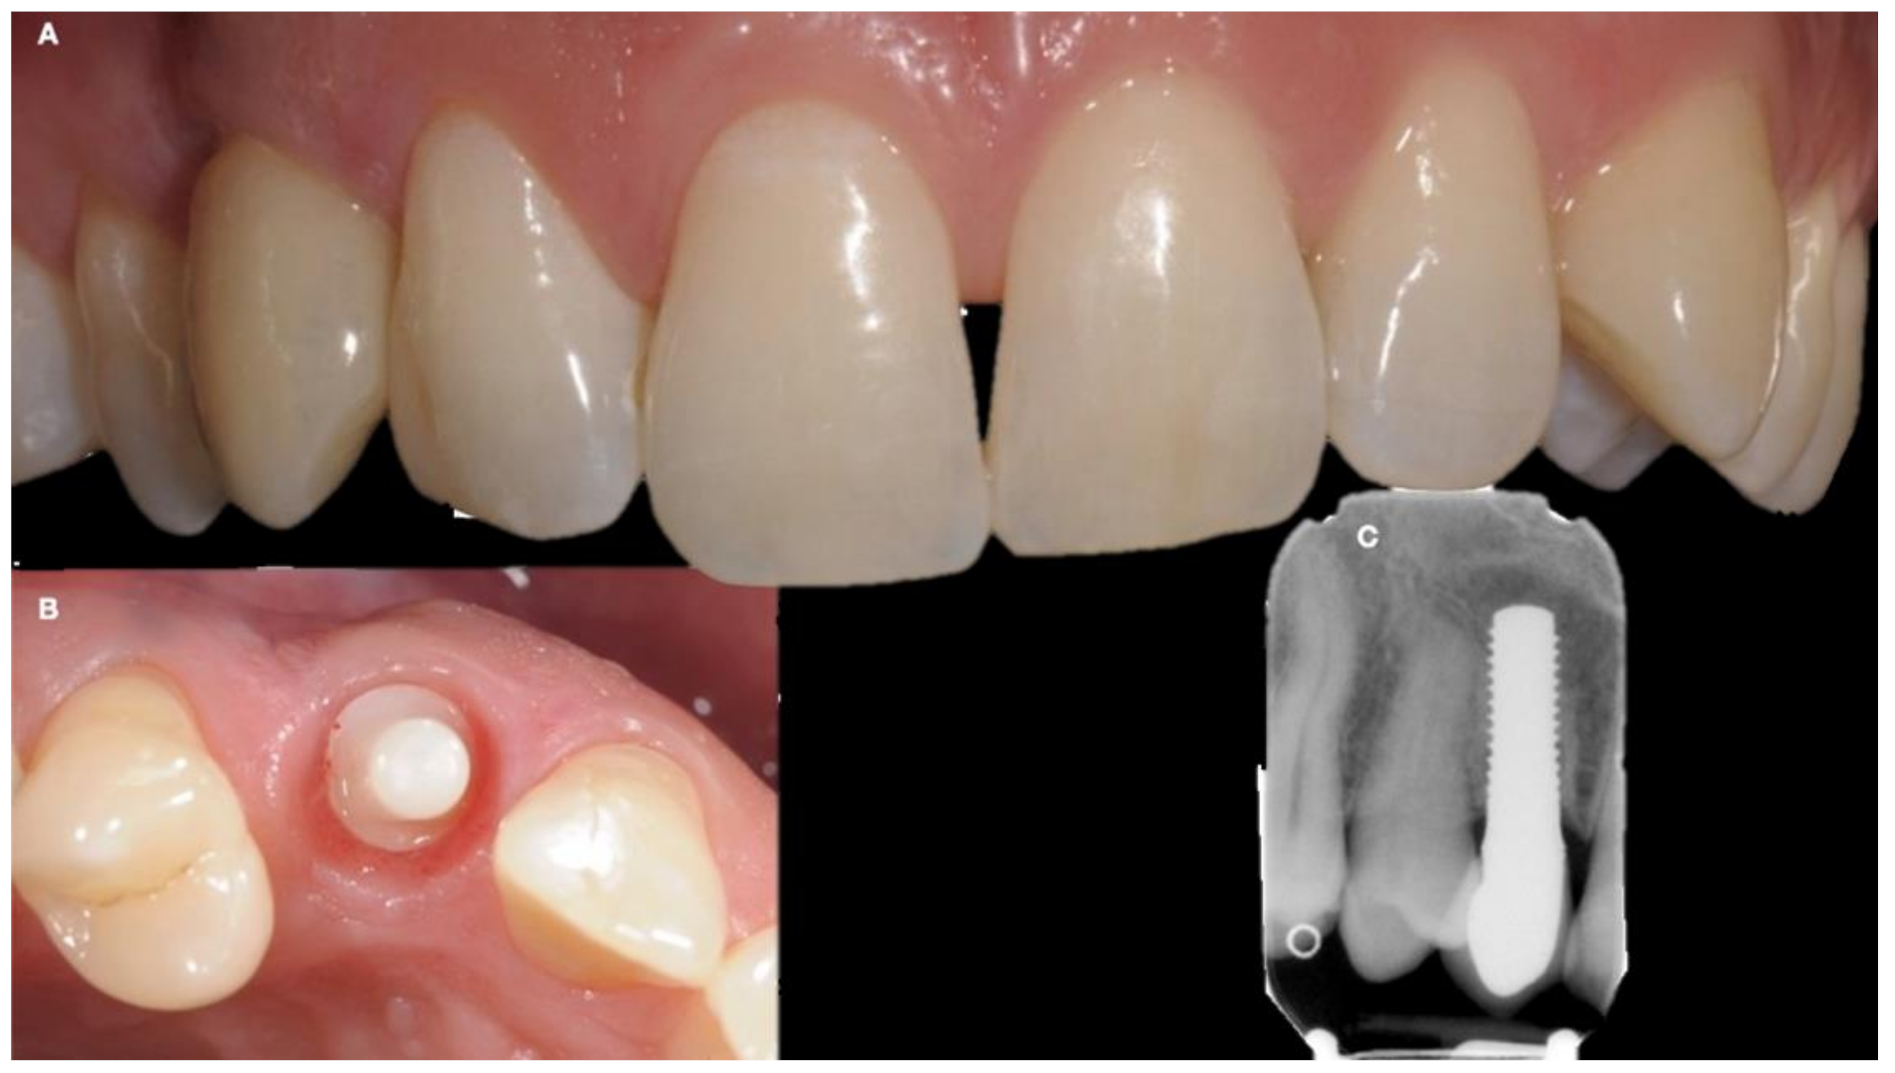

| (a) Surgical removal of the deciduous tooth and orthodontic extrusion, and taking in occlusion of the permanent canine |

| (b) Conservative treatment of the deciduous tooth living in situ with the impacted canine |

| (c) Removal of the deciduous tooth and involvement of the adjacent natural elements for a fixed conventional or adhesive bridge living in situ with the impacted canine |

| (d) Removal of the deciduous tooth and replacement with implant-borne-prosthesis living in situ with the impacted canine, accepting the compromise of involving the impacted tooth in the implant seating procedure |

| (e) Surgical removal of the impacted canine and, in a second stage, removal of the deciduous tooth and replacement with implant-borne-prosthesis |